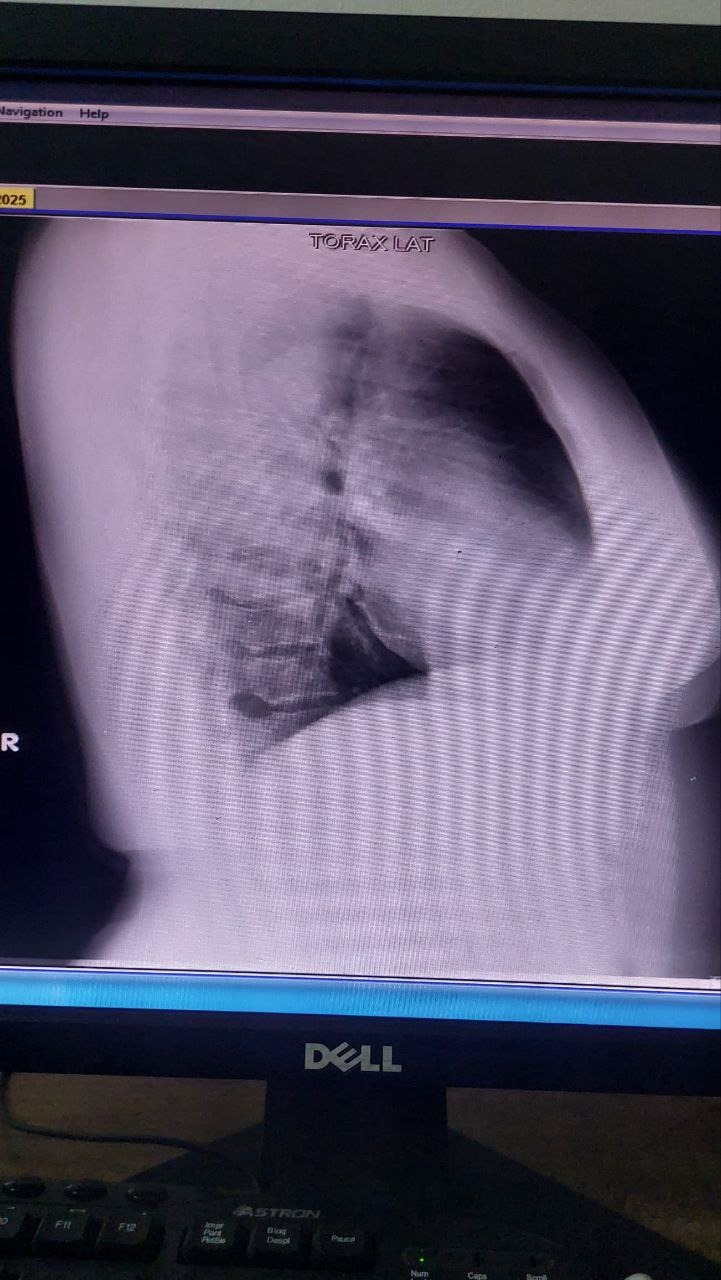

Ya el primer gran paso fue dado, su quimioterapia. En este segundo paso, Aida esta apta para ser intervenida quirúrgicamente, luego de haber recibido sus ciclos de quimioterapia, que han sido duros, pero no imposibles, estamos recaudando para poder realizar su MASTECTOMIA PARCIAL ONCOLOGICA, RECONSTRUCCION Y DISECCION AXILAR IZQUIERDA.

The first big step has already been taken: her chemotherapy. In this second step, Aida is ready for surgery. After receiving her chemotherapy cycles, which have been difficult but not impossible, we are raising funds to support her oncological partial mastectomies, reconstruction, and left axillary dissection.